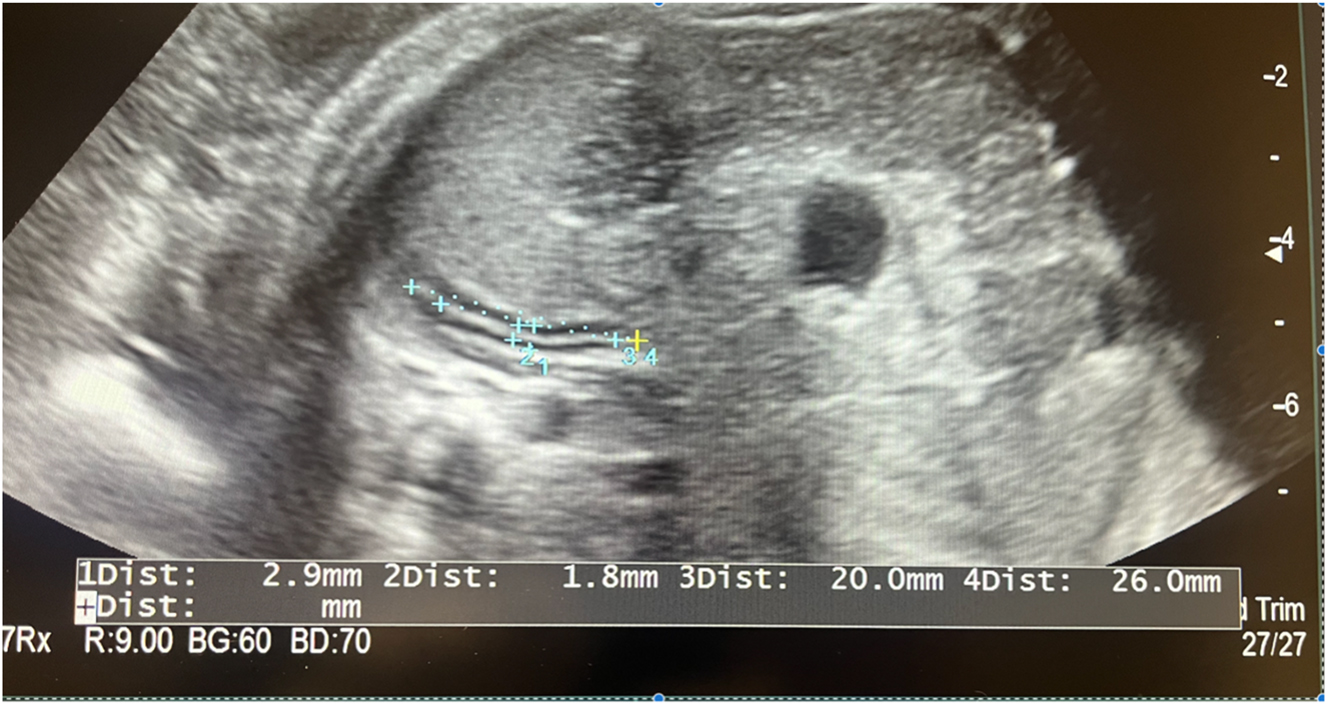

Jakkapop Kanjak, Ratana Komwilaisak, Piyamas Saksiriwuttho, Kiattisak Kongwattanakul, Sukanya Chaiyarach, Chatuporn Duangkum, Termtem Waidee

Page range: 1286-1295